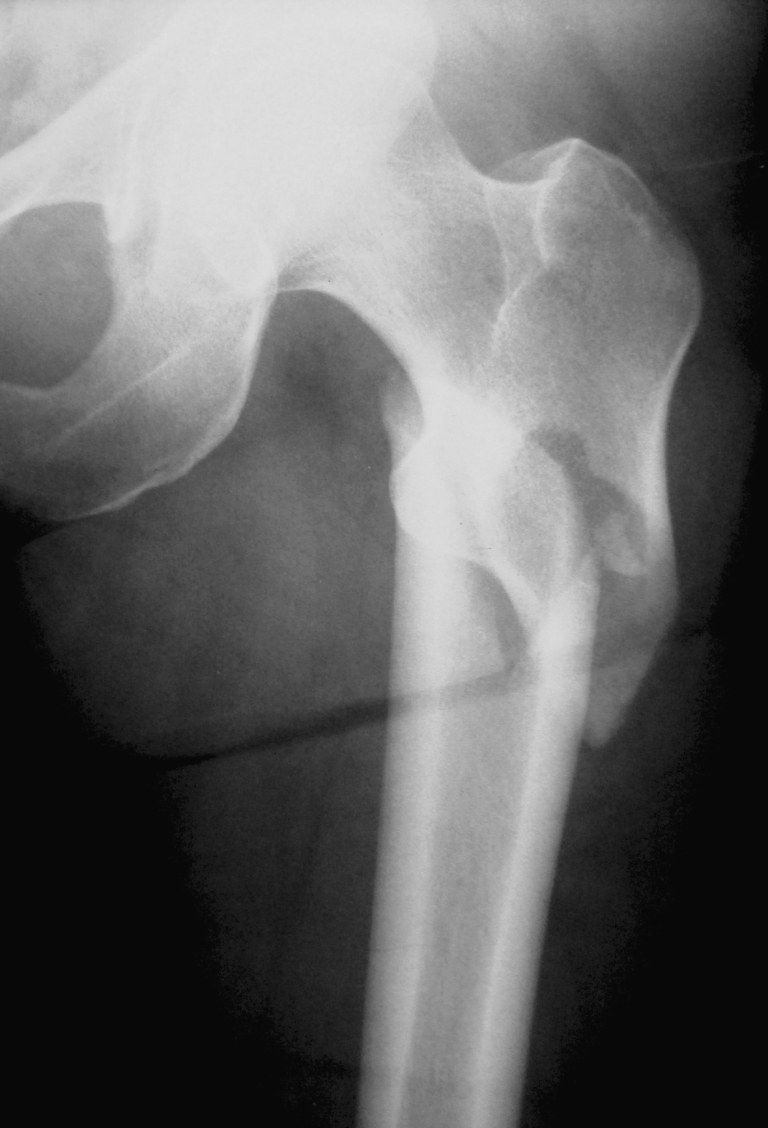

The initial and follow-up radiographs of a sample case are presented in Figs. 1, 2, 3.

Fig. 1.

Preoperative anterior-posterior proximal femur X-ray of the sample case